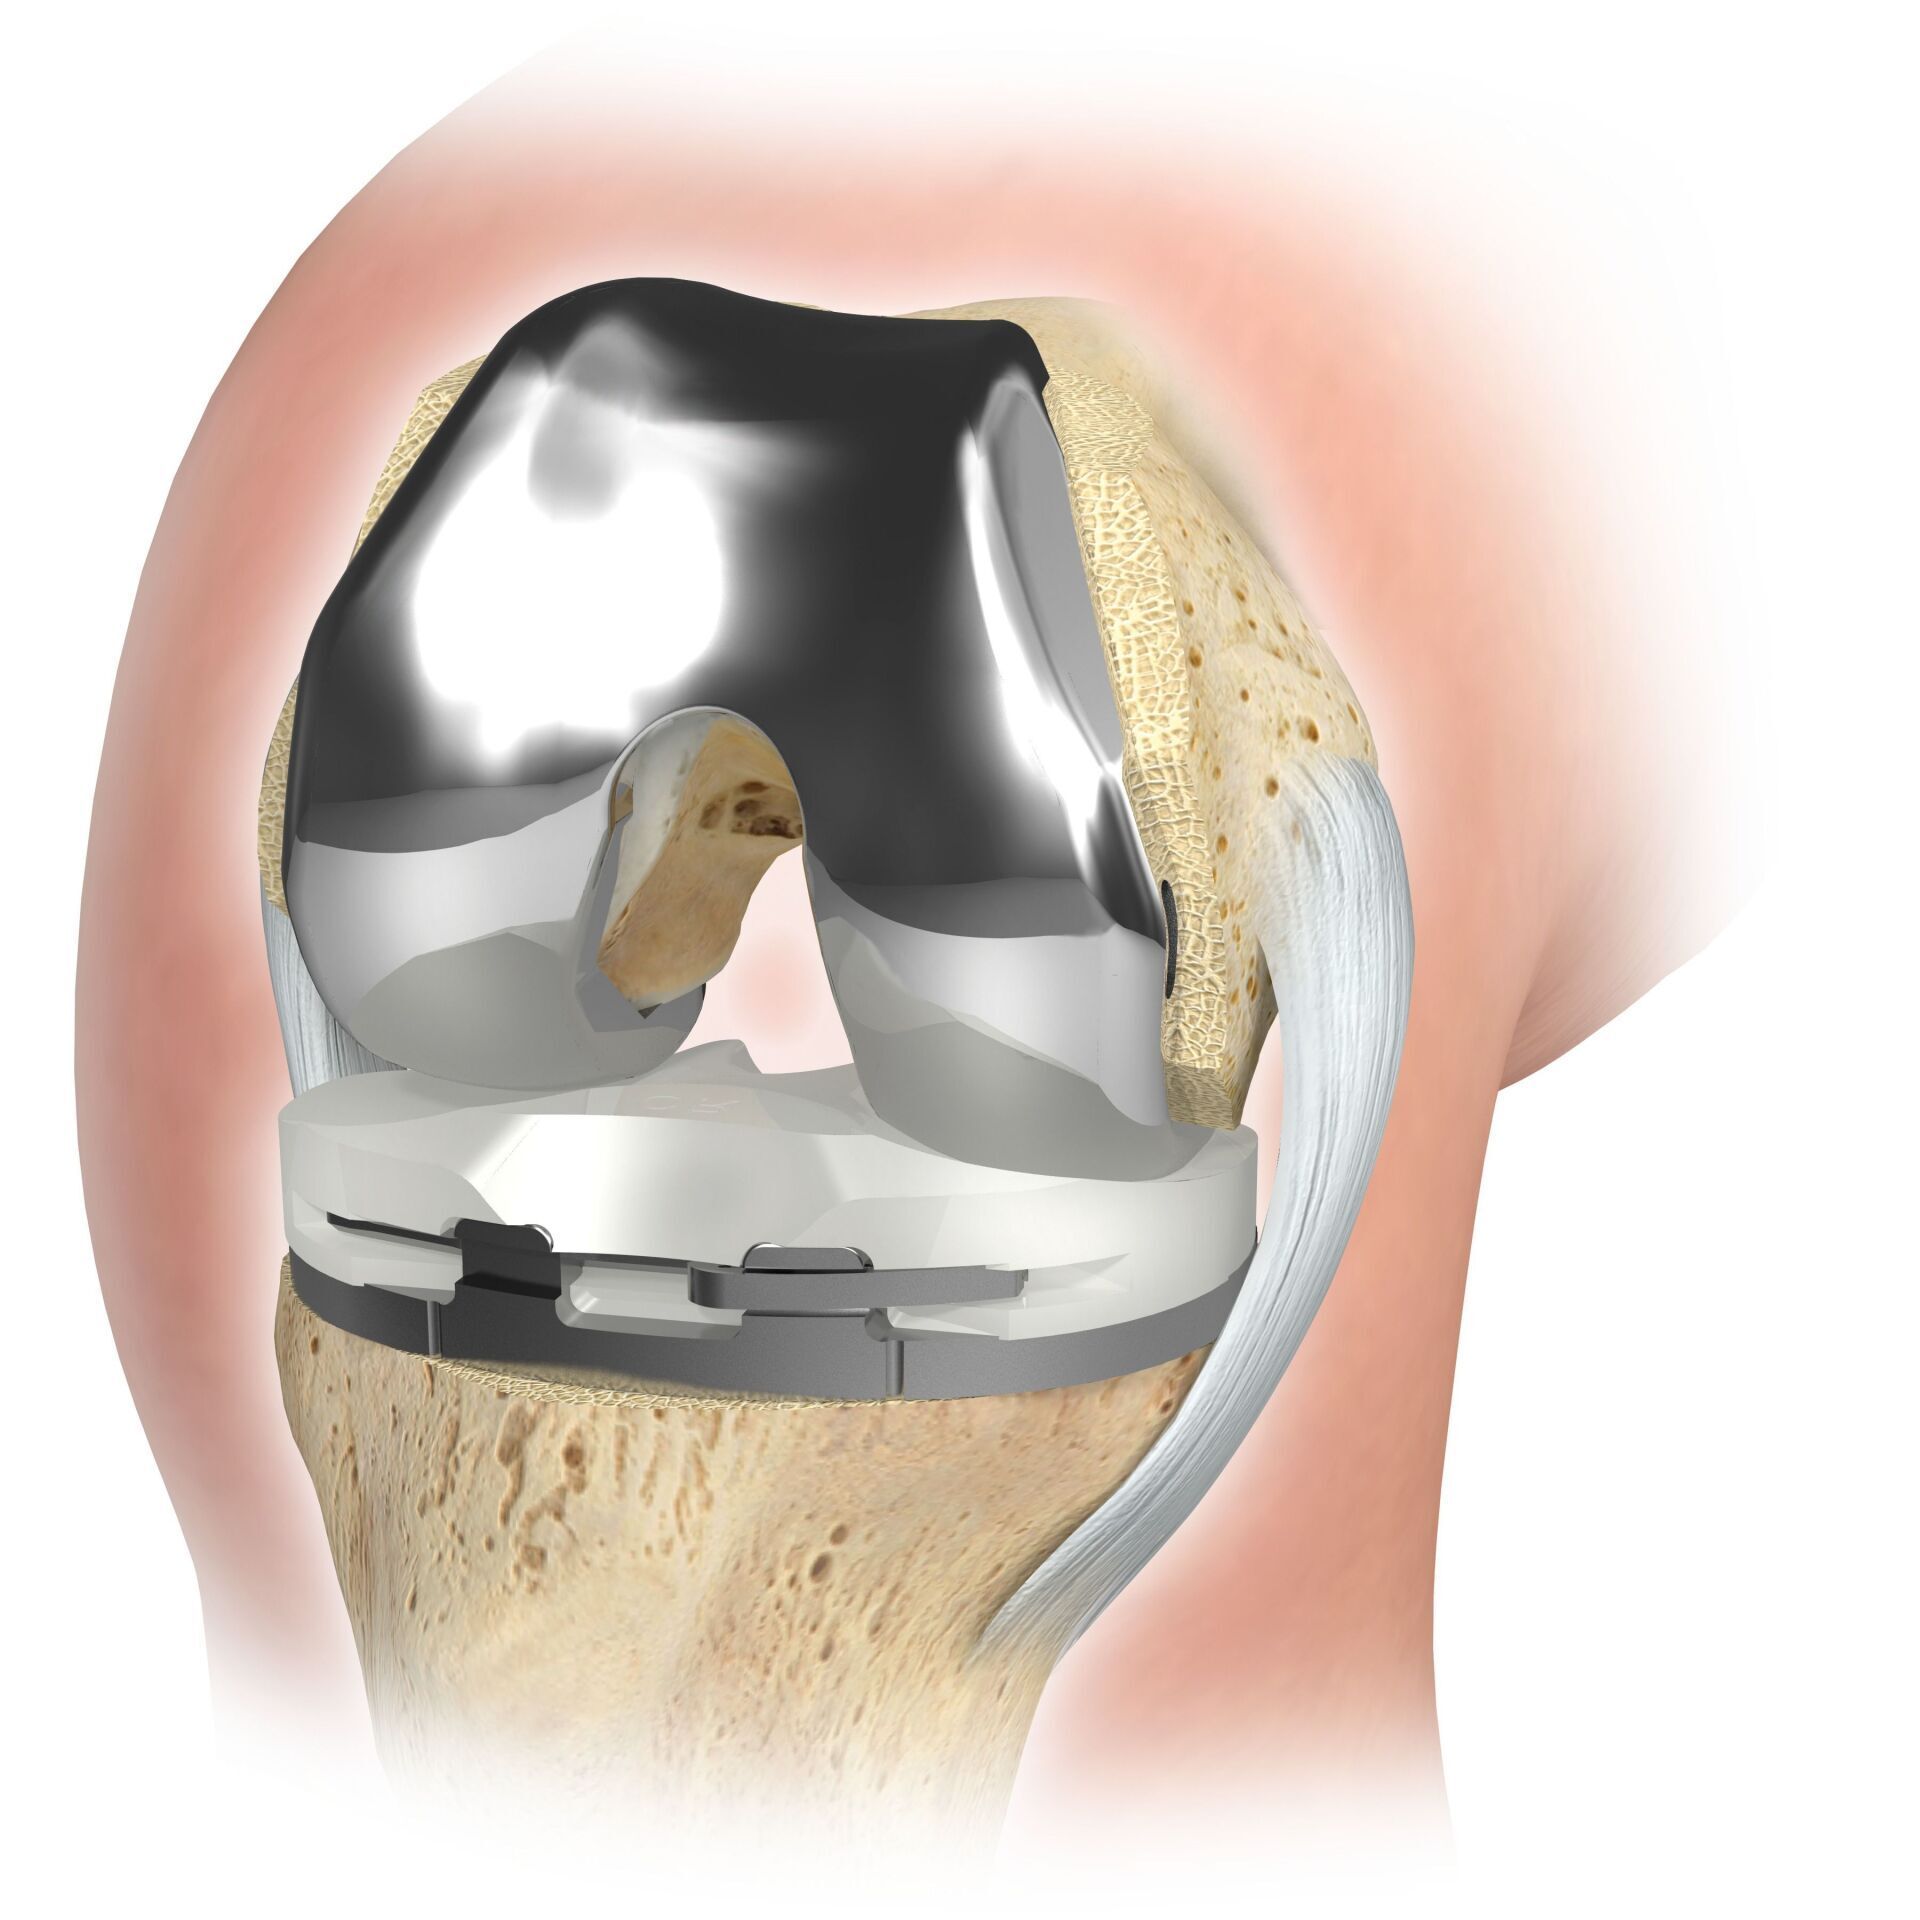

La articulación de rodilla artificial reemplaza la superficie del cartílago destruida por la osteoartritis. El hueso subyacente del fémur y la cabeza tibial permanece intacto. Algunos comparan una articulación artificial moderna de rodilla con la coronación de un diente; el término exacto es el llamado rejuvenecimiento bicondilar. Entre las nuevas superficies de la parte superior e inferior de la pierna se encuentra la llamada incrustación de un plástico blanco especialmente endurecido, que en la imagen de rayos X se puede ver como la distancia entre las piezas metálicas.